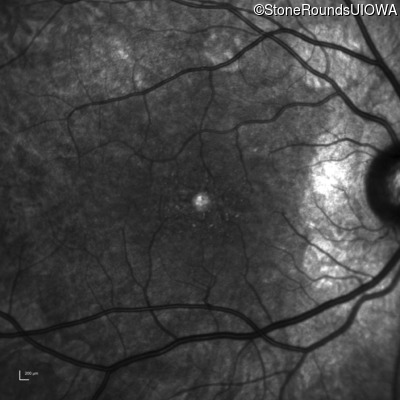

Infrared Fundus Photograph - Right - 20/20 -3

Exemplar